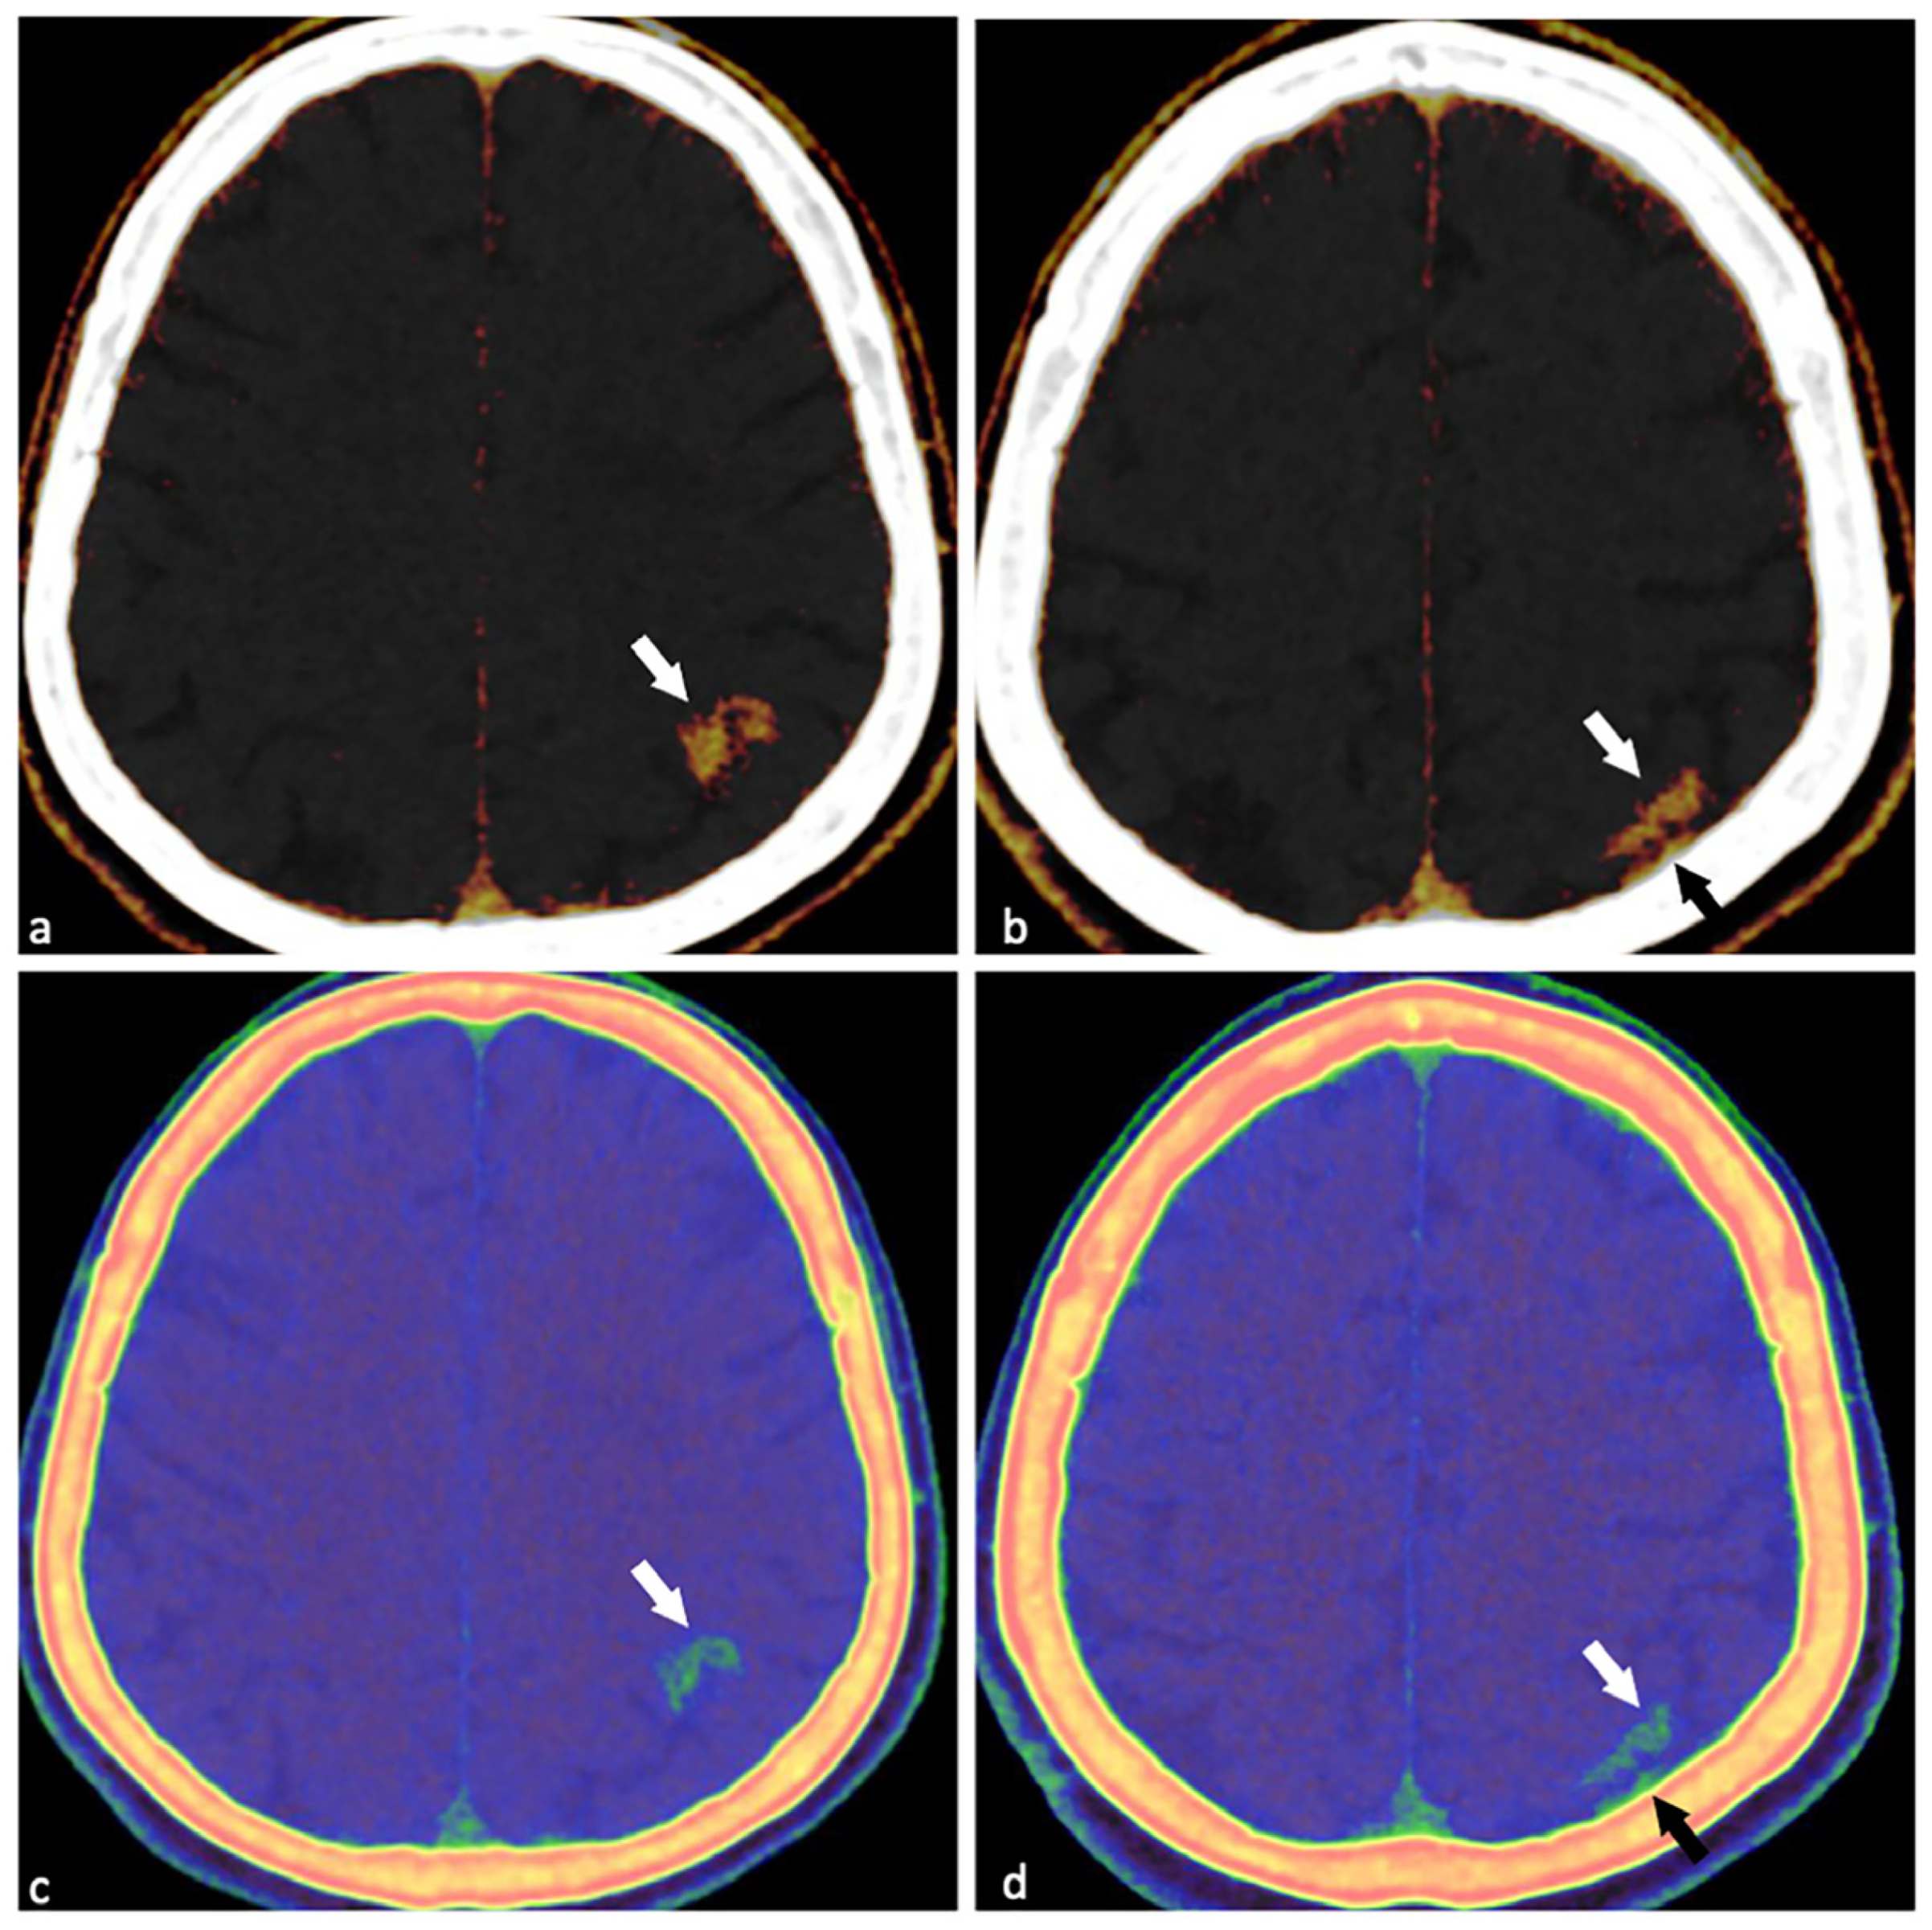

Dual-Energy Computed Tomography (DECT) for Diagnosing Contrast-Induced Encephalopathy (CIE) Mimicking Intracranial Hemorrhage (ICH): A Rare Case

Shen, Y.; Ye, T. Dual-Energy Computed Tomography (DECT) for Diagnosing Contrast-Induced Encephalopathy (CIE) Mimicking Intracranial Hemorrhage (ICH): A Rare Case. Diagnostics 2025, 15, 2426. https://doi.org/10.3390/diagnostics15192426